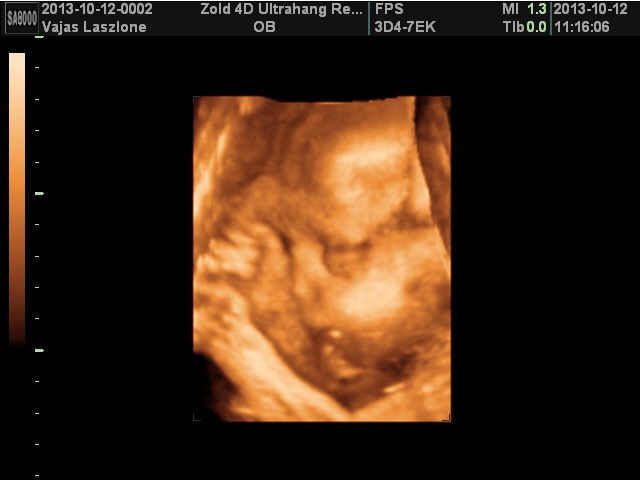

Én most 29 hetes vagyok, azaz holnap töltöm be. Nálam minden rendben van, ultrahangom 5 hete nem volt, de hétfőn megyünk 4D- re, már nagyon várom, mert még egyenlőre nem teljesen biztos hogy kislány, de majd remélem mostmár kiderül. A cukorterhelésem rendben volt, a vizeletemben nekem is volt baktérium, de nincs jelentősége, majd kedden újra megnézik.

Nagyon ficánkolós a picikém, a hidegfrontknál szinte szambázik a hasamban. Nos a hízásom is beindult már 7 kg plusszom van, szerintem ez még nem sok, mert igazából nem is látszik ratam csak a hatalmas pocim. A környezetemben aztmondják nagyobb a hasam mint kelene, na de nem baj az, lényeg hogy minden rendben legyen. Eléggé lent van a pocim, de gondolom ennek nincs jelentősége. Én még méreteket nem tudok hogy mekkora most a babám, na de majd hétfőn kiderül a 4D-n.